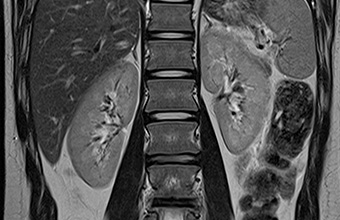

MR u onkologiji

MR u onkologiji poseban je program snimanja bez kojeg je danas nezamislivo rano otkrivanje različitih tumora, raka, nadzor odgovarajućih terapija i kontrola oporavka nakon složenih operacija.